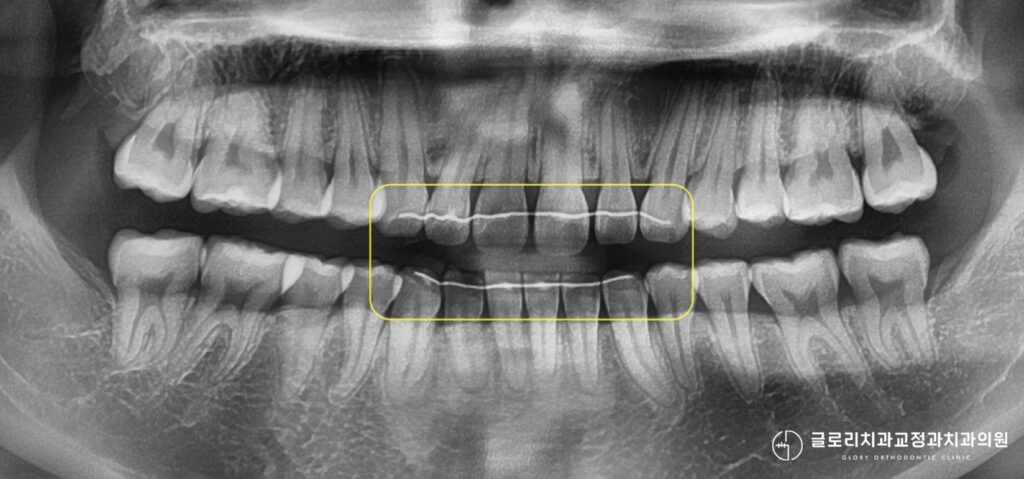

이 기간 동안 보정장치 착용이 소홀해지면 다음처럼 재발로 인한 치아 벌어짐으로 치아 재교정이 필요해지는데 한 번 틀어진 치아는 통제가 어려운 상황이 될 수 있습니다.

재교정 후에는 벌어졌던 앞니 사이 공간이 닫히며 다시 가지런해진 치열을 확인할 수 있습니다.